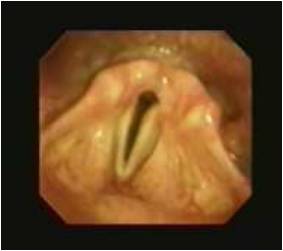

19 下图中所见的喉部是一个成年的

A. 男性

B.  女性

C.  马

19B

显示的喉头属于一个成年女性。 “声门裂”前方的三角形(声带之间中间的空间)清晰可见。一个男性的声带通常比女性的更厚,如果病人作深呼吸会注意到更外展,男性的声带开放更大(平均约有19毫米)。成年妇女的声门裂通常小于男性(一般女性的声门裂外展最大的直径为12毫米)。 声带随着呼吸移动,而位于上方的前庭皱襞不会。例如马,吸气时如果没有环杓展肌的作用,显著降低压力会引起喉的塌陷。在运动的时候,由于气流,持续久收缩这些肌肉把环杓软骨和声带拉伸,使喉头扩张。 一些马匹发育被称为喉返偏瘫。在这种情况下,环杓背肌麻痹导致环杓软骨受影响的一侧塌陷到喉头,在吸气时阻塞气道。顺便提一下,人类也有类似的发现!然而,不像马常常是遗传的,人常常由于肿瘤、感染、或外伤导致的。